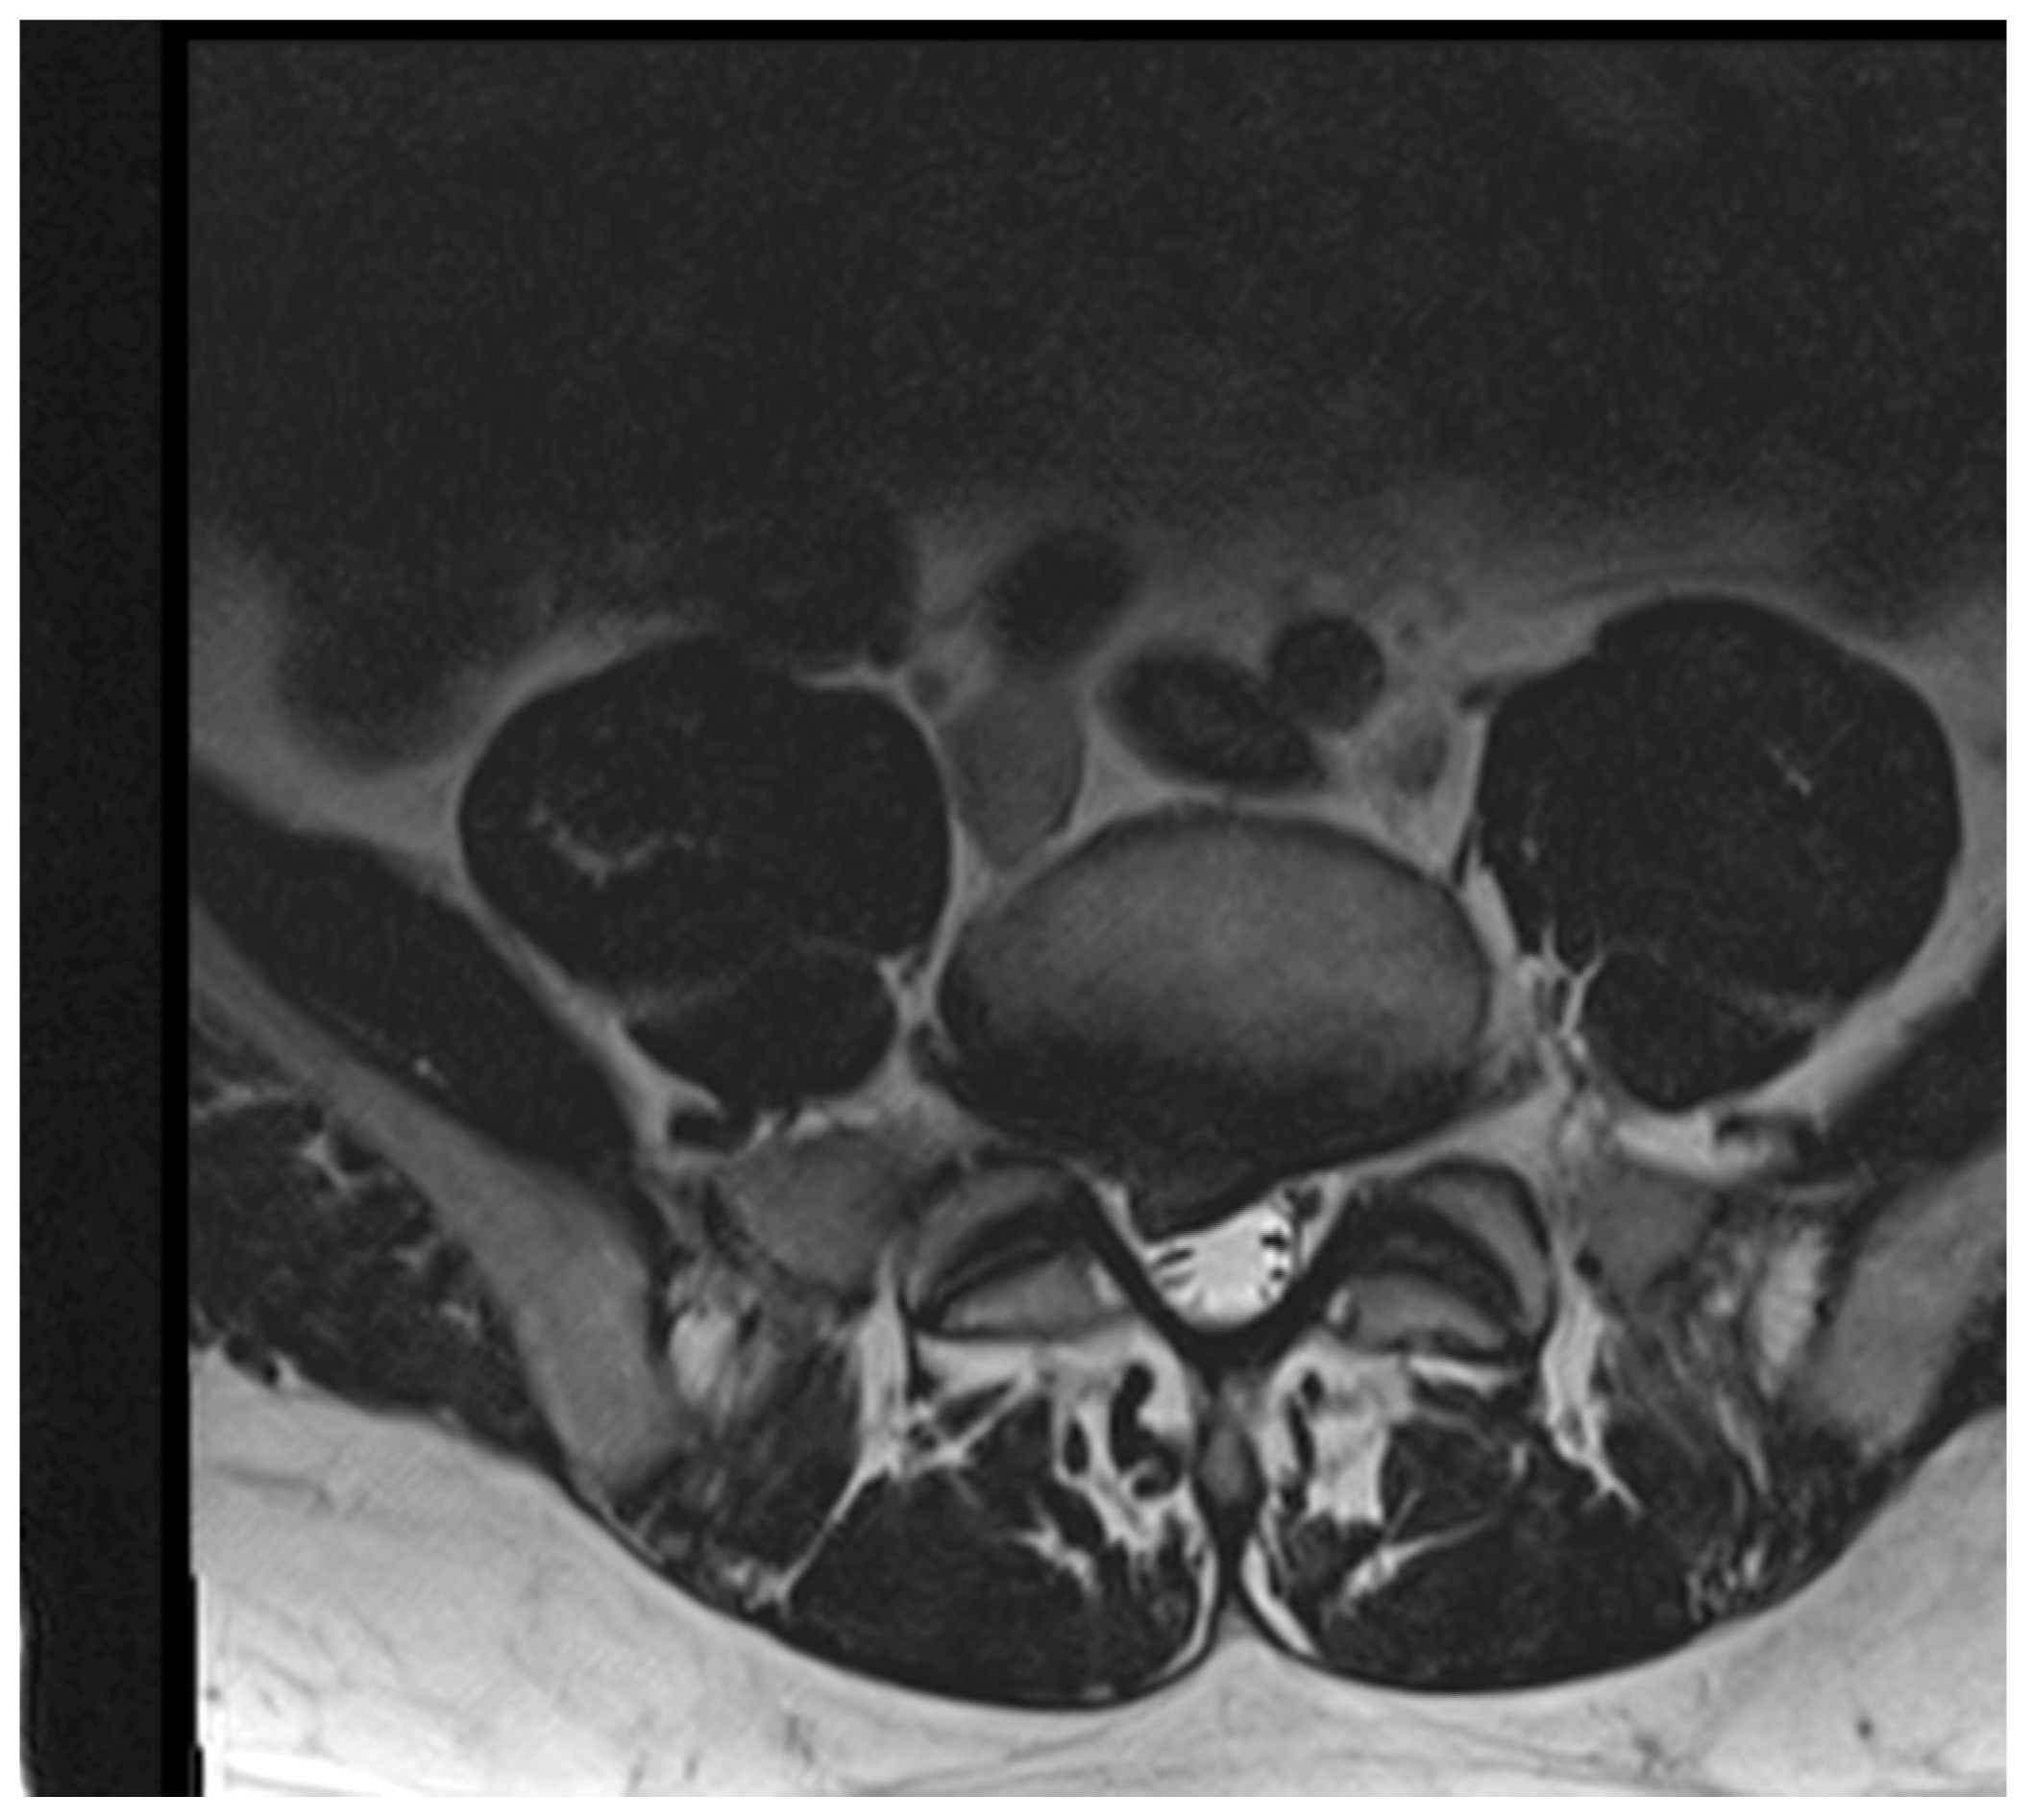

2.3. Lumbar Disc Herniation